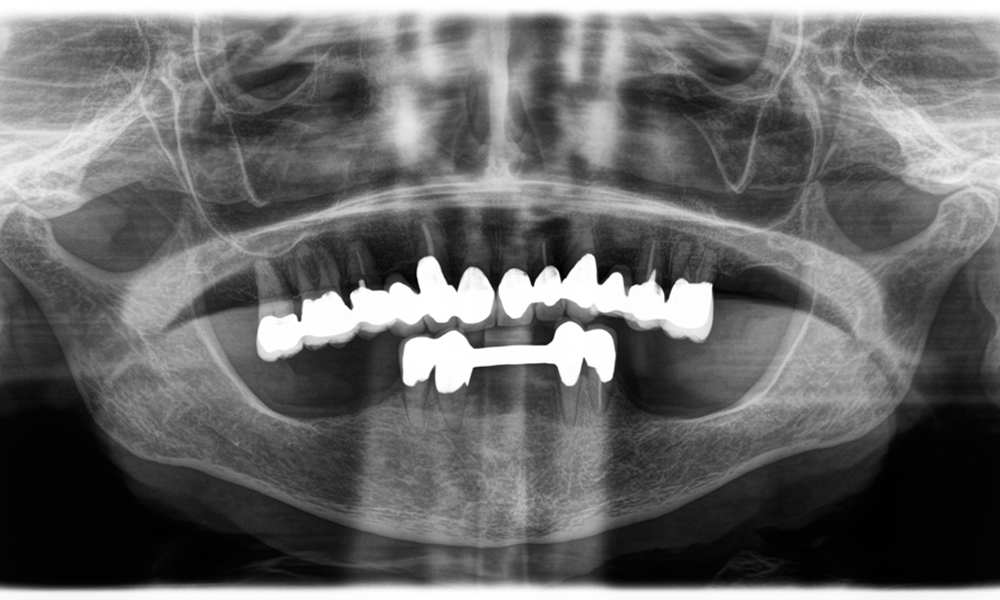

El reto consistía en extraer doce coronas bloqueadas con aleación común sin dañar los raigones subyacentes. Se utilizó el contra-ángulo para realizar incisiones precisas en las capas de cerámica y separar las estructuras metálicas con una fresa de metal duro, con el fin de extraer las coronas con un traumatismo mínimo. En solo 30 minutos se retiraron las coronas antiguas y se pudo preparar el nuevo trabajo, compuesto por zirconio completo en la zona posterior y coronas con recubrimiento en la zona anterior. El resultado fue una reconstrucción completa, satisfactoria tanto desde el punto de vista funcional como estético (véase la fig. 1).

Otro ejemplo del rendimiento clínico de Power Edition fue la sustitución de una corona de zirconio dañada en una paciente de 63 años. El daño se produjo debido a la rotura de una parte del revestimiento de la corona de zirconio de 20 años de antigüedad en el diente 6. A pesar de encontrarse en la zona posterior, a la paciente le molestaba y deseaba una nueva corona.